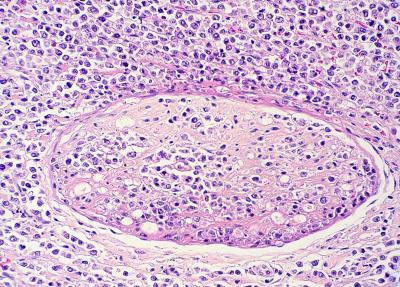

Este estudio, publicado en Transboundary and Emerging Diseases (2020; doi:10.1111/tbed.13713), ilustra el papel de la patología como herramienta de apoyo a los programas de conservación para especies en peligro de extinción. En este caso, la detección de dos herpesvirus presumiblemente nuevos en visones europeos se realizó a raíz del diagnóstico de un caso de linfoma principalmente neural/perineural con cuerpos de inclusión característicos de herpesvirus intralesionales en un visón europeo procedente del programa de cría en cautividad de esta especie amenazada. Estos virus podrían tener una influencia en el desarrollo de ésta y otras enfermedades que afectan a esta especie en cautividad y, por lo tanto, afectar a sus poblaciones.